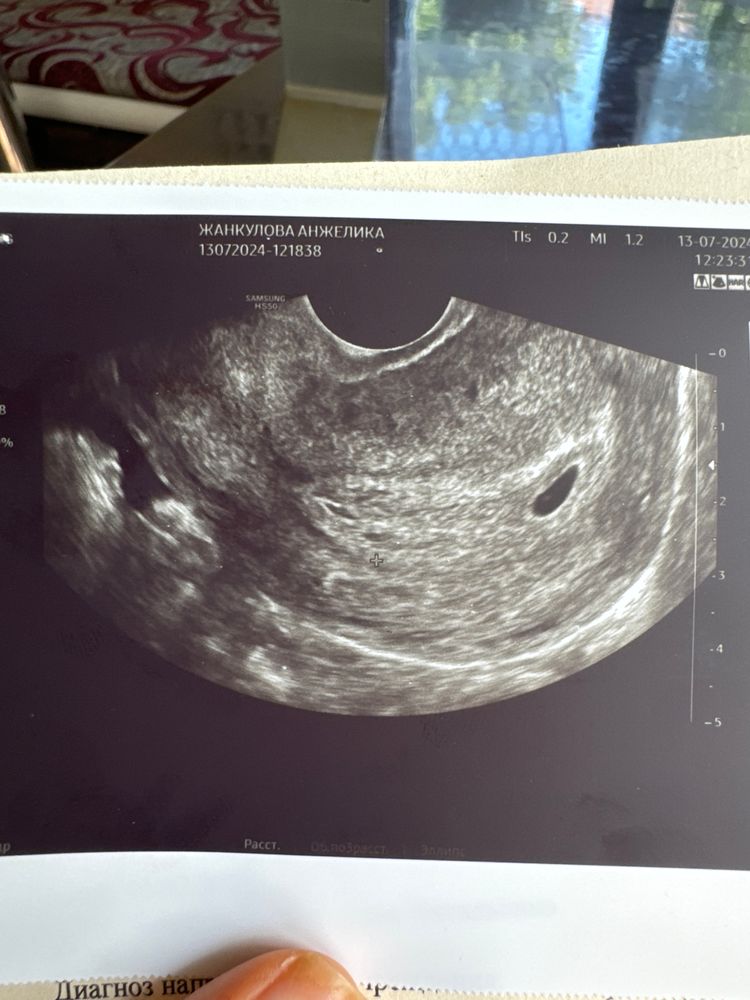

По узи 3 недели

Всем привет! Сегодня по акушерскому сроку 5 недель и 4 дня. Была первый раз на узи, подтвердили 3 недели. Хгч сдавала, прирост отличный. В 4и 6 был 678, в 5и 1 стал 1560. Плодное яйцо 7,5мм. Но ни эмбриона ни желтого тела нет. Сказали прийти через 2 недели. Как думаете, появится? У кого так было?

У меня тоже 5 недель сейчас, позавчера ПЯ 7мм и ЖМ 2 мм, эмбриона пока не видно

В 5 недель ровно только ПЯ 3,5 мм. В 7 недель уже эмбрион 9,6мм и жм 3,5 мм. Тоже переживала, еле выждала эти 2 недели.